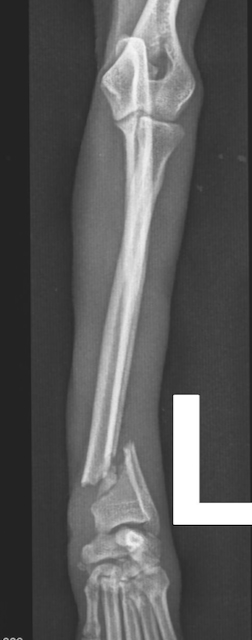

Der Unfall war typisch für Zwerghunde. Aufgeregt war Hugo (Name geändert) so lange zwischen den Beinen seines Halters herumgewuselt, bis dieser ihm aus Versehen aufs Beinchen trat. Die Folge: Der gerade mal 2,3 Kilo schwere Prager Rattler landete mit einem offenen Unterarmbruch auf dem OP-Tisch von Dr. Klaus Zahn. Mit einer feinen, dem zarten Körperbau angemessenen Platte versorgte dieser die Fraktur, und Hugo wurde nach Hause entlassen.

Doch drei Wochen später wurde der kleine Hund erneut im Notdienst vorgestellt: Beim Gassigehen hatte er auf einmal gelahmt. Die Ursache: ein Ermüdungsbruch der Metallplatte. „An Hugo sieht man, was passiert, wenn der tierärztliche Rat zur Ruhigstellung nicht befolgt wird“, sagt Dr. Klaus Zahn. „Übermäßige Aktivität hatte die Platte überlastet.“ Denn der Prager Rattler durfte viel zu früh wieder frei im Zimmer herumlaufen und sogar vom Sofa springen. „So kleine Hunde gehören für vier bis sechs Wochen in einen Laufstall, damit die Knochen stabil heilen können“, erklärt der Orthopäde.